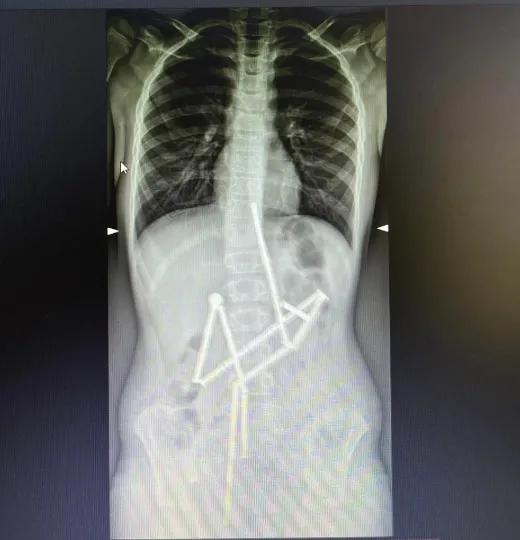

До НДСЛ “Охматдит” у Києві звернулися батьки дитини, що скаржилась на біль у животі. Вже на першому рентген-знімку спеціалісти побачили наявність у травному каналі цілої групи сторонніх тіл, у яких вдалось впізнати магнітний конструктор. 20 магнітів знаходились у різних частинах шлунково-кишкового тракту, проте були зʼєднані між собою.

Лікарі прийняли рішення про проведення невідкладного оперативного втручання. Медикам вдалося захопити перший магніт і витягти його разом із ланцюжком з 18 елементів конструктора. Проте один магніт залишився й спеціалісти не мали змоги видалити його ендоскопічно.

Надалі почали працювати хірурги. Була виконана лапаротомія та ретельна ревізія органів черевної порожнини. Всі отвори були закрито, а магніт видалено. Зараз дитина проходить післяопераційний курс лікування та реабілітації.